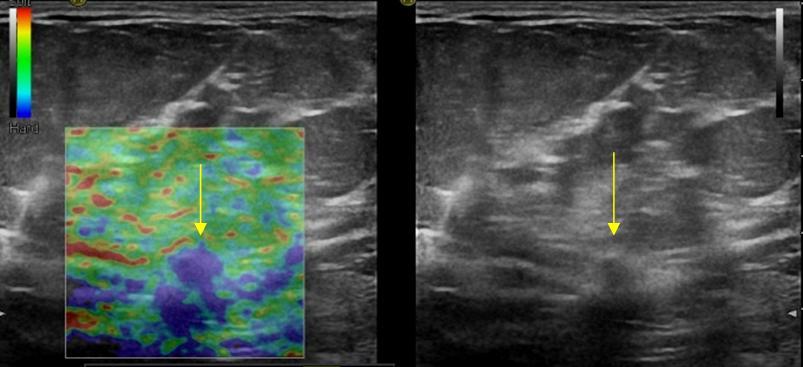

Ung thư vú

Ung thư vú - Ảnh 2

» Thông tin: Nữ giới – 62 tuổi.

» Lâm sàng: Kiểm tra sức khỏe.